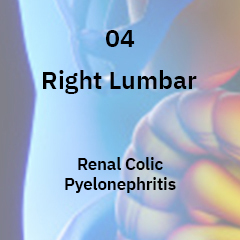

This is a functional GI disorder with symptoms to the mid or lower gastrointestinal tract, including the irritable bowel syndrome (IBS), functional abdominal bloating, constipation, diarrhea, and unspecified functional bowel disorder.

This is a common disorder that affects the large intestine. Signs and symptoms include cramping, abdominal pain, bloating, gas, and diarrhea or constipation, or both. IBS is a chronic condition that you’ll need to manage long term.